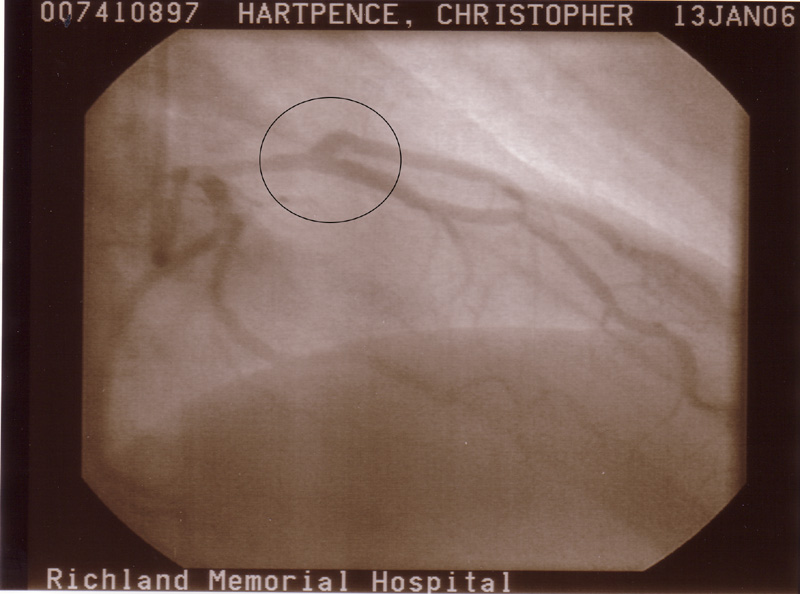

At this point I am getting aggravated. I see him everyday. He was getting worse. He was hurting while we were in the office right then. So he told the Doctor that he was hurting now. So they did yet another EKG and had the stress test results sent to the ASAP and sure enough they were abnormal and he was admitted to the hospital at about 2 o'clock. He was sent straight to the cath lab where they went in to take pics. (Pics to follow) And if something was found they were going to fix it right then.

They found something. Somthing that was reffered to as a plaque rupture. Plaque in your arteries is like the buildup on your teeth. Apparently that goop ruptured and got all over everywhere and clogged up two different places that kind of branch off.

They placed two stints in those and ballooned another place.